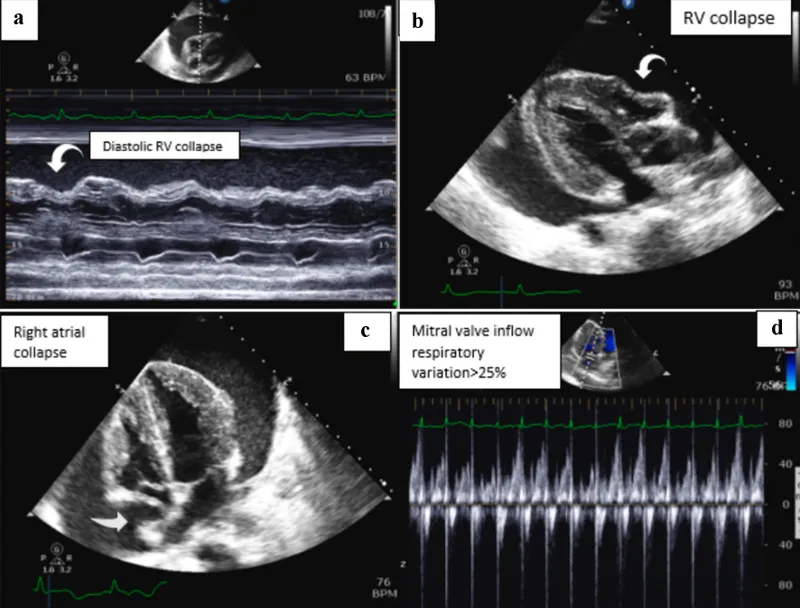

⭐ Echocardiography is the gold standard, revealing effusion size and diastolic collapse of the right atrium/ventricle-the most specific sign of tamponade.